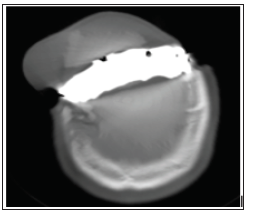

The authors present a craniotomy for removal of a left frontal lesion growing on a titanium cranioplasty. This 66-year-old doctor was injured in the Ararb-Israeli 1973 War. He was a tank driver and his tank were the last tank to suffer a direct hit from a mortar bomb shell during the war. He underwent urgent surgery and a right frontal craniectomy in Egypt, leaving a titanium plate as a bone graft instead of his frontal bone which was removed during surgery. 4 years prior to this admission, a frontal subcutaneous bossing on the patent’s frontal bone appeared. It was indolent until 2 years prior to admission when it demonstrated continued growth. The tumor’s last dimensions prior to surgery were measured at 9cm width over 5cm length. This 66-year-old male sustained a head injury in 1973. However, he continued to live a normal, fulfilling life. Being the first student in his class to graduate medical school after being in a rehab institution for combat soldiers. The patient was recently admitted to our service to undergo surgery for removal of a superficial subcutaneous lesion which presented as a cosmetic problem. The patient denied headaches, seizures or any other neurological complaint, however the appearance greatly disturbed him, enough to undergo surgery and removal of the lesion. Prior to surgery, the patient underwent a Computed Tomography (CT) scan which demonstrated an extra-axial lesion adherent to the patient’s titanium plate (Figures 1 & 2).

Figure 1: An axial CT scan in the bone window displaying the patient’s lesion which can be seen on top of the patient’s titanium plate.